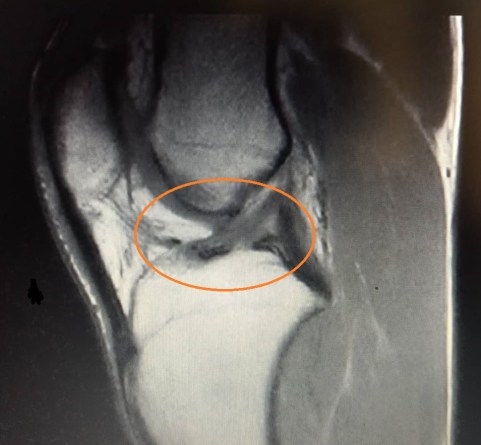

Figura 4: RMN dopo 9 mesi dello stesso atleta della Figura 3 dopo trattamento conservativo

Con un periodo di riabilitazione tra i 3 e i 6 mesi potresti concludere un percorso conservativo, ci saranno dei parametri per capire quando riprendere anche a correre e a fare sport, che sono simili per la ripresa nel post operatorio e ve ne parlerò in quel capitolo. Il principio di questo trattamento è sempre stato che migliorando la forza muscolare e la propriocezione si potesse in qualche modo sopperire alla lesione del legamento perché si pensava che non avesse alcuna capacità di guarigione (a causa della scarsa vascolarizzazione), in realtà si è visto che ci sono delle possibilità di miglioramento delle condizioni della stessa struttura lesionata, in particolare in persone con più di 20 anni che hanno effettuato il trattamento conservativo:

Nella tabella effettuata in uno studio del 2017 (Ihara 2017), dove per tipo di infortunio si intendeva da (tipo I) a molto severo (tipo IV) e grado del recupero un dato analogo (12 mesi dopo), dove nel grado I abbiamo un legamento continuo, fino al grado IV dove il legamento è ancora del tutto compromesso, possiamo notare che diversi atleti hanno migliorato la morfologia del loro legamento (in particolare dei 34 atleti con infortunio di tipo II 16 sono arrivati al grado I, situazione di normalità).